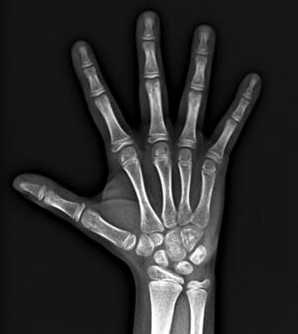

Ortho X - Radiografia de Mão e Punho

É utilizada para avaliação da idade óssea fazendo a medição dos ossos da mão e punho, através do método de Eklof e Ringertz.